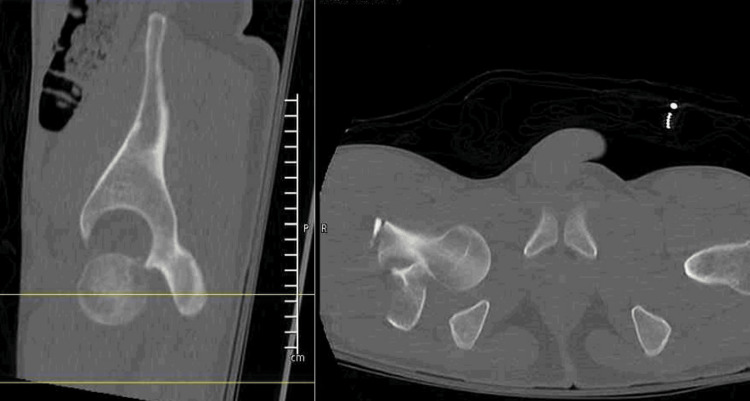

Direct inferior hip dislocation is the rarest type, sometimes referred to as luxatio erecta. To the author's knowledge, an adult inferior hip dislocation with an associated displaced intertrochanteric fracture has only been reported once in the literature. Accordingly, there are few described treatment options for this injury. An 18-year-old male presented after a motor vehicle collision with an inferior hip dislocation and an associated ipsilateral intertrochanteric hip fracture. He was taken to the operating room urgently for the reduction of the dislocation and definitive treatment. In this case, a fracture table was utilized along with a Schanz pin to reduce the hip dislocation and for the reduction and intramedullary nailing of his intertrochanteric fracture.

Abstract Image